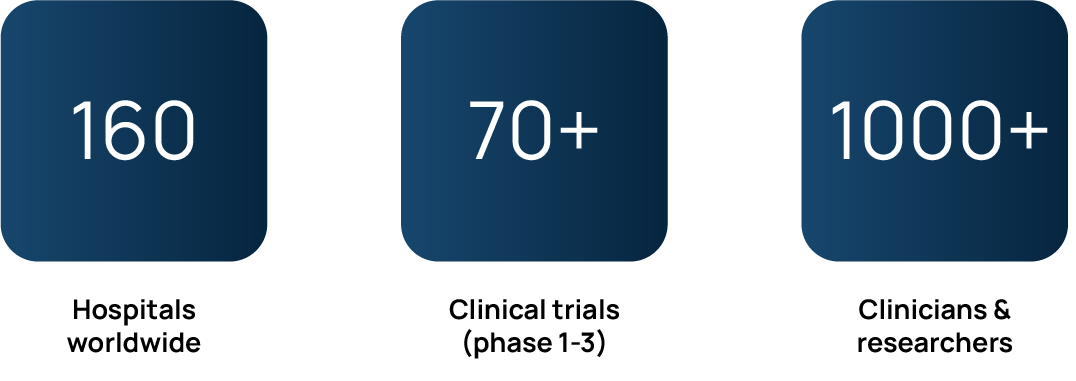

Strong track record

We have a solid track record in the life sciences industry. QP-Insights® has successfully delivered reliable solutions to meet the data management, storage, and processing needs of our clients.

QP-Insights & EUCAIM

QP-Insights is the backbone platform for 9 EU-wide research consortiums such as EUCAIM, a cornerstone of Europe’s Beating Cancer Plan and is already trusted by major biopharmaceutical companies. Ultimately, these collaborative efforts advance our mission of advancing precision medicine and patient health.